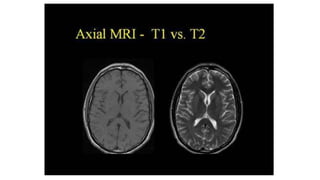

MR Image appearance

• The easiest way to identify the T1WI and T2WI is to look the fluid

filled space in the body like CSF fluid in brain ventricles, synovial

fluids, free fluid in abdomen etc.

• Fluids appear dark on the T1 weighted image while appears bright on

T2 weighted image.